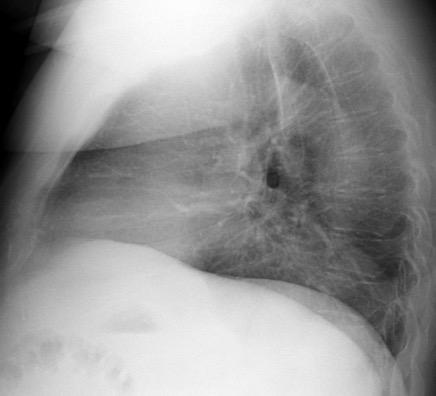

Atelectasia crónica de LLI en paciente con enfermedad neuromuscular.

Puede acompañarse de atelectasia del LII.

Benjamin JJ et al. . Left lower lobe atelectasis and consolidation following cardiac surgery: the effect of topical cooling on the phrenic nerve. Radiology 1982